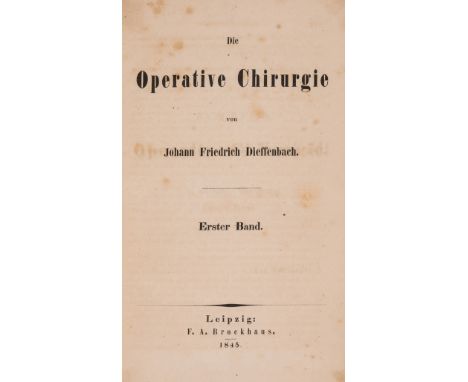

Dieffenbach (Johann Friedrich) Die Operative Chirurgie, 2 vol., first edition, half-titles, browned, contemporary half roan, rubbed, rebacked preserving old spines, corners renewed, [Wellcome II.466], Leipzig, 1845-48 § Tilanus (C.B.) Schets der Heelkunde tot leiddraad voor zijne lessen, first edition, presentation copy from the author to his medical teacher B.T.Suerman inscribed on front free endpaper, with other ink signatures and J.van der Hoeven bookplate, portion cut away from final imprint leaf, original cloth-backed boards, rubbed, Amsterdam, 1835; and 5 others, medicine, 8vo (8)⁂ Dieffenbach is important for his work in reconstructive surgery, making significant advances in the procedures and techniques of plastic surgery.